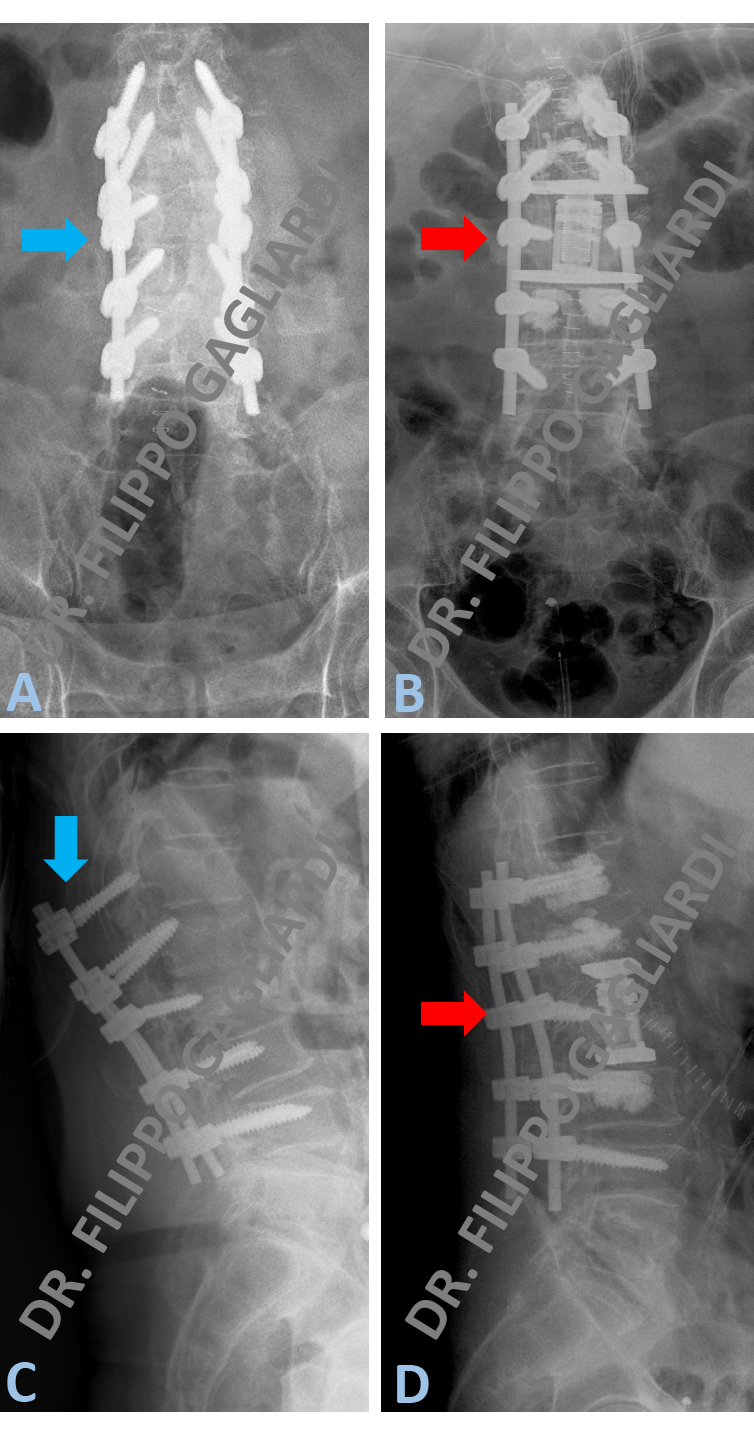

Corpectomia vertebrale lombare Caso di cedimento di un sistema di stabilizzazione vertebrale in seguito ad incidente stradale. Le frecce azzurre nelle Figure A e C dimostrano lo scivolamento posteriore del sistema.

Per ricostituire la stabilità vertebrale il Paziente è stato sottoposto a revisione del sistema con asportazione di un corpo vertebrale rotto (corpectomia). In seguito questo verrà sostituito con una gabbia in titanio (cage) (frecce rosse Figura B e C).